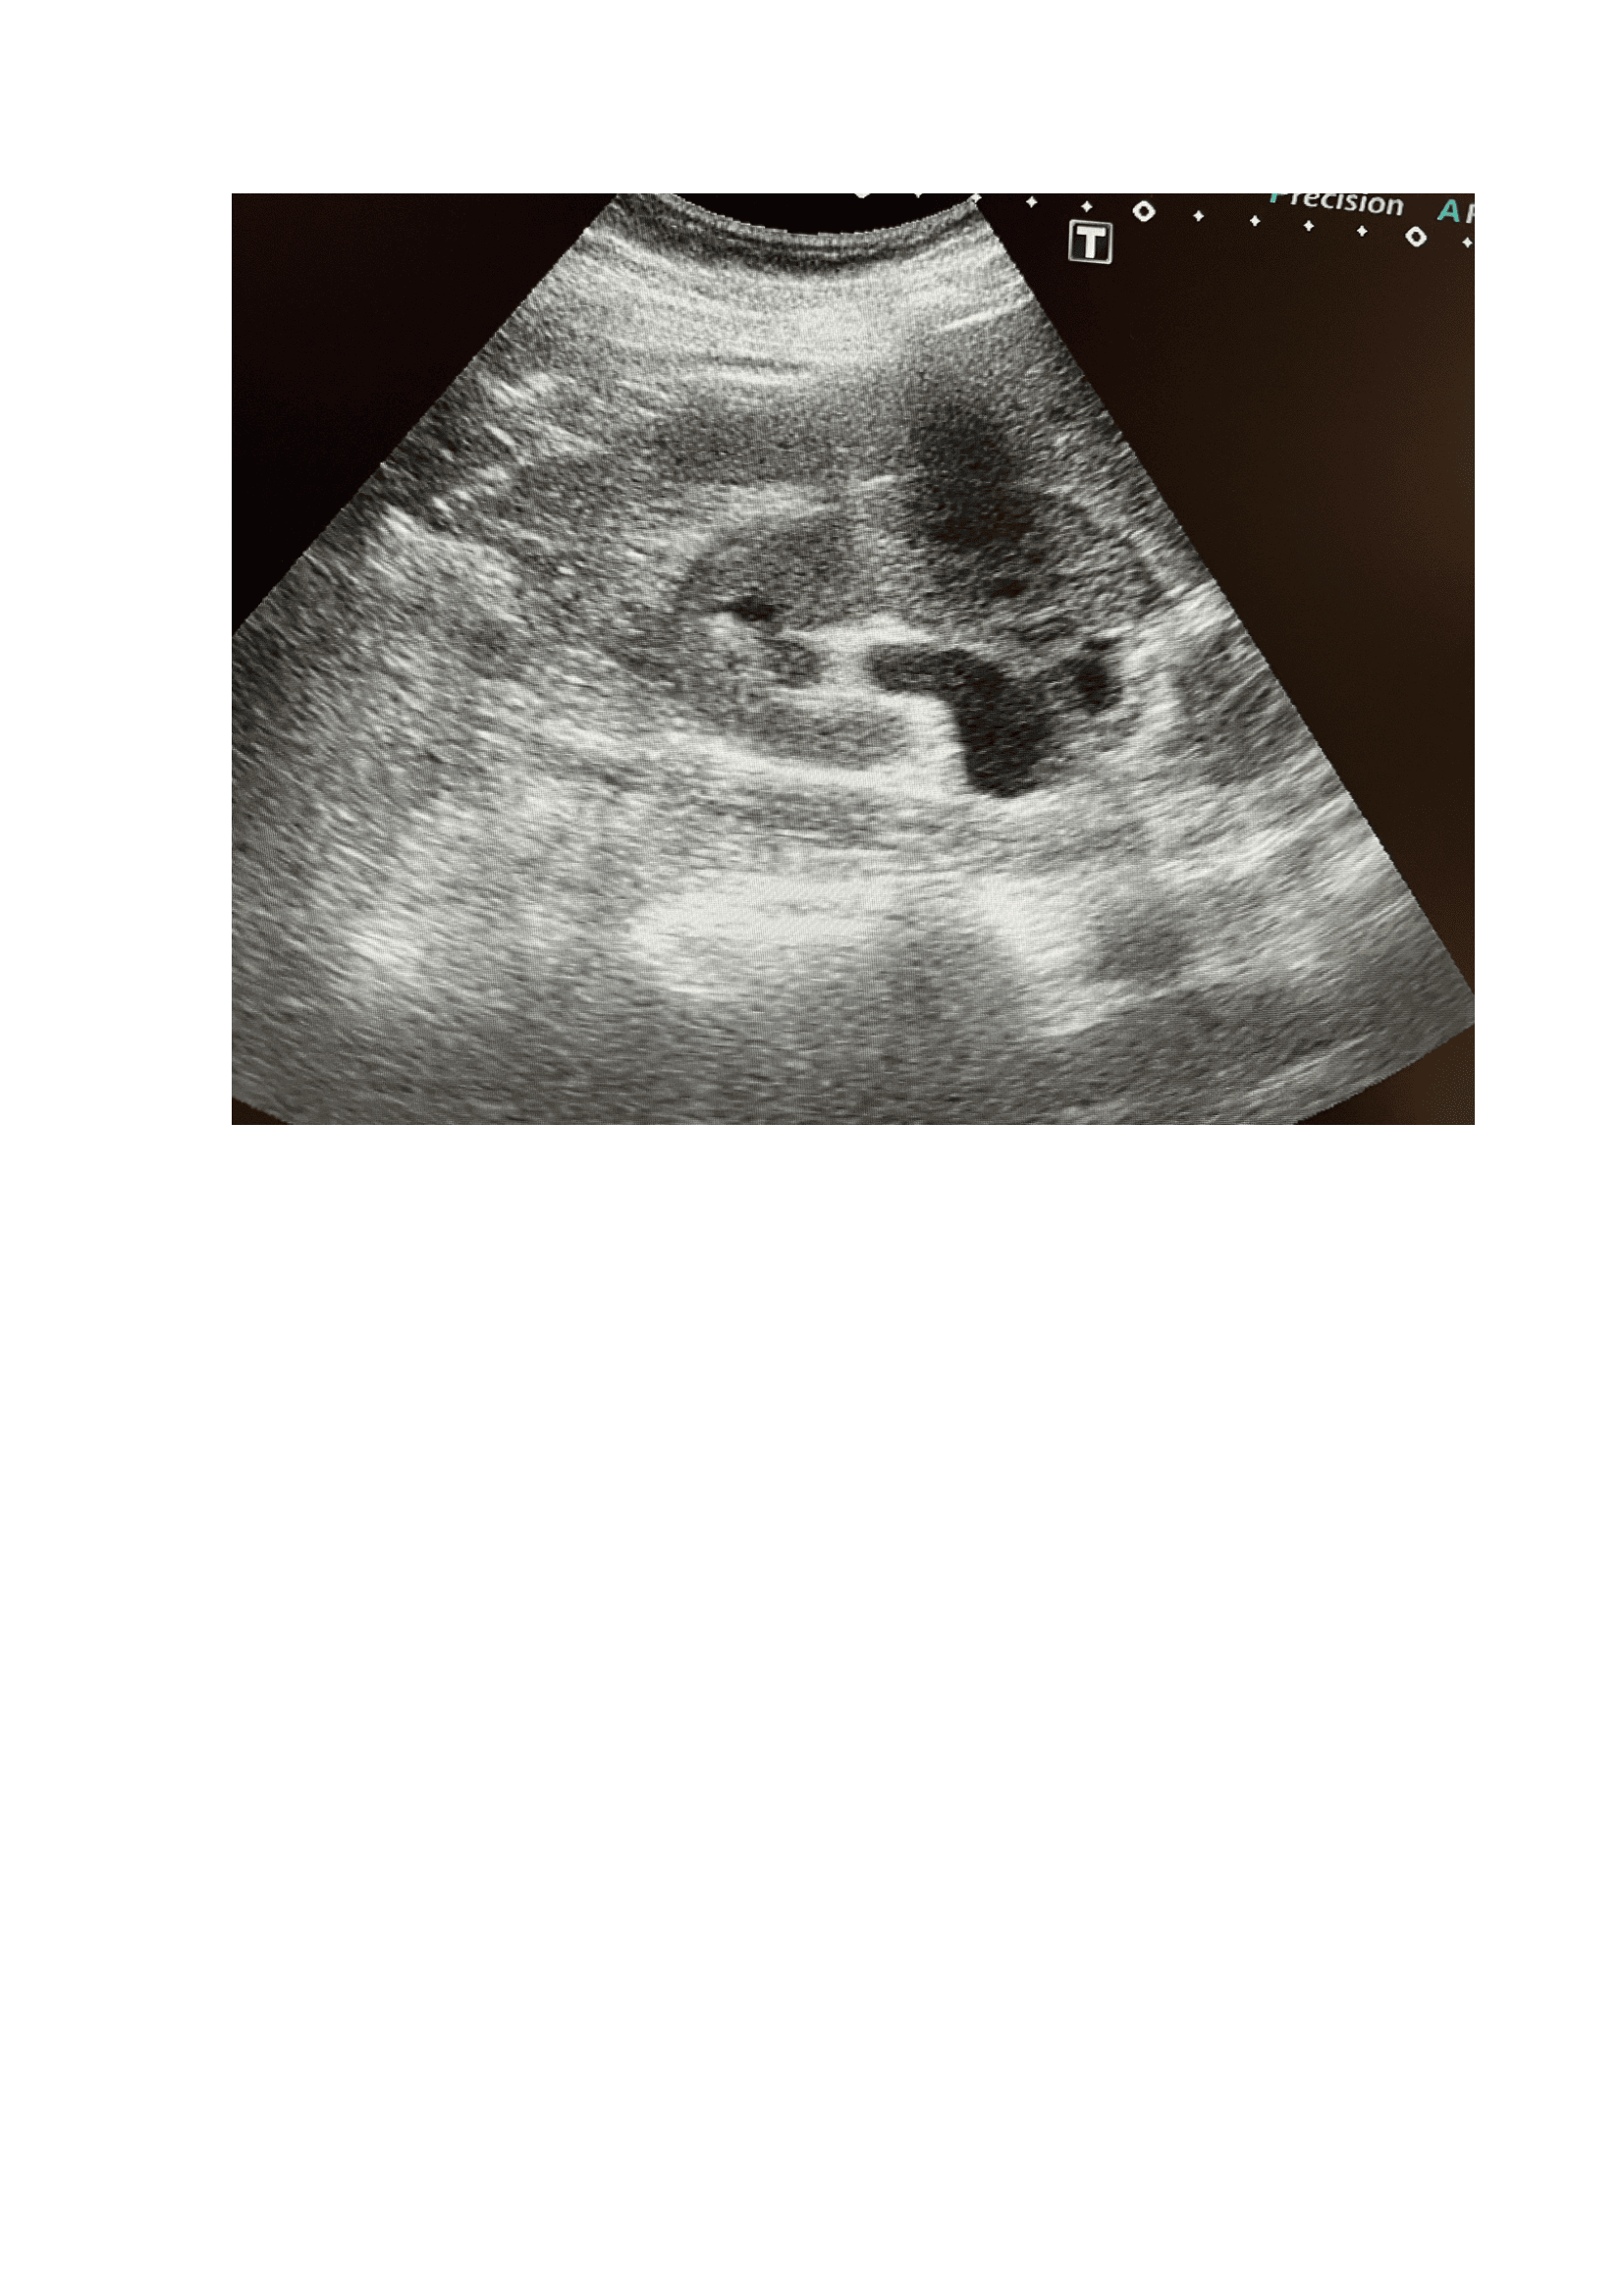

Exploración física, fiebre (39,5 °C) y taquicardia (FC: 120), puño-percusión positiva en la fosa lumbar derecha, sugiriendo una patología renal. Se realiza POCUS) que revela un riñón derecho aumentado de tamaño con una imagen lítica compatible con un cálculo renal de 1,2 cm x 8 mm, junto con dilatación de la pelvis renal (hidronefrosis grado I-II). Una tomografía computarizada (TAC) confirma los hallazgos y muestra un cálculo renal de 4 mm en la zona vesicoureteral distal, no obstruyendo totalmente la vía urinaria.